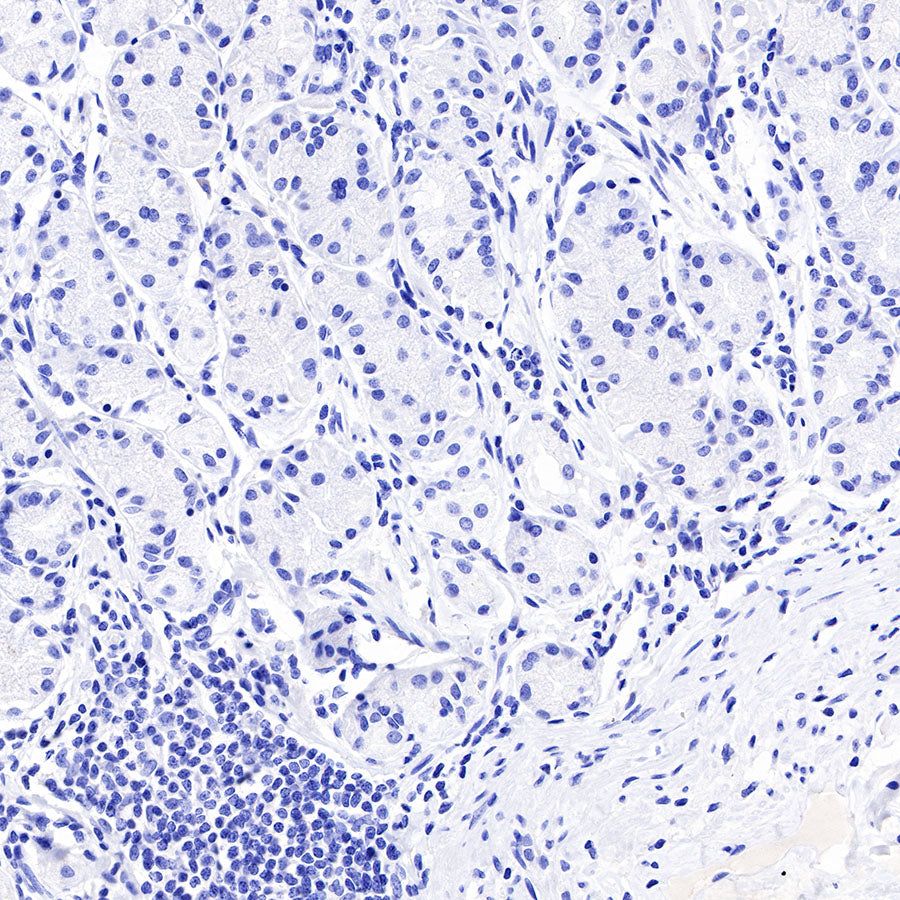

IHC shows positive staining in paraffin-embedded human placenta. Anti-PAPP-A antibody was used at 1/1000 dilution, followed by a HRP Polymer for Mouse & Rabbit IgG (ready to use). Counterstained with hematoxylin. Heat mediated antigen retrieval with Tris/EDTA buffer pH9.0 was performed before commencing with IHC staining protocol.